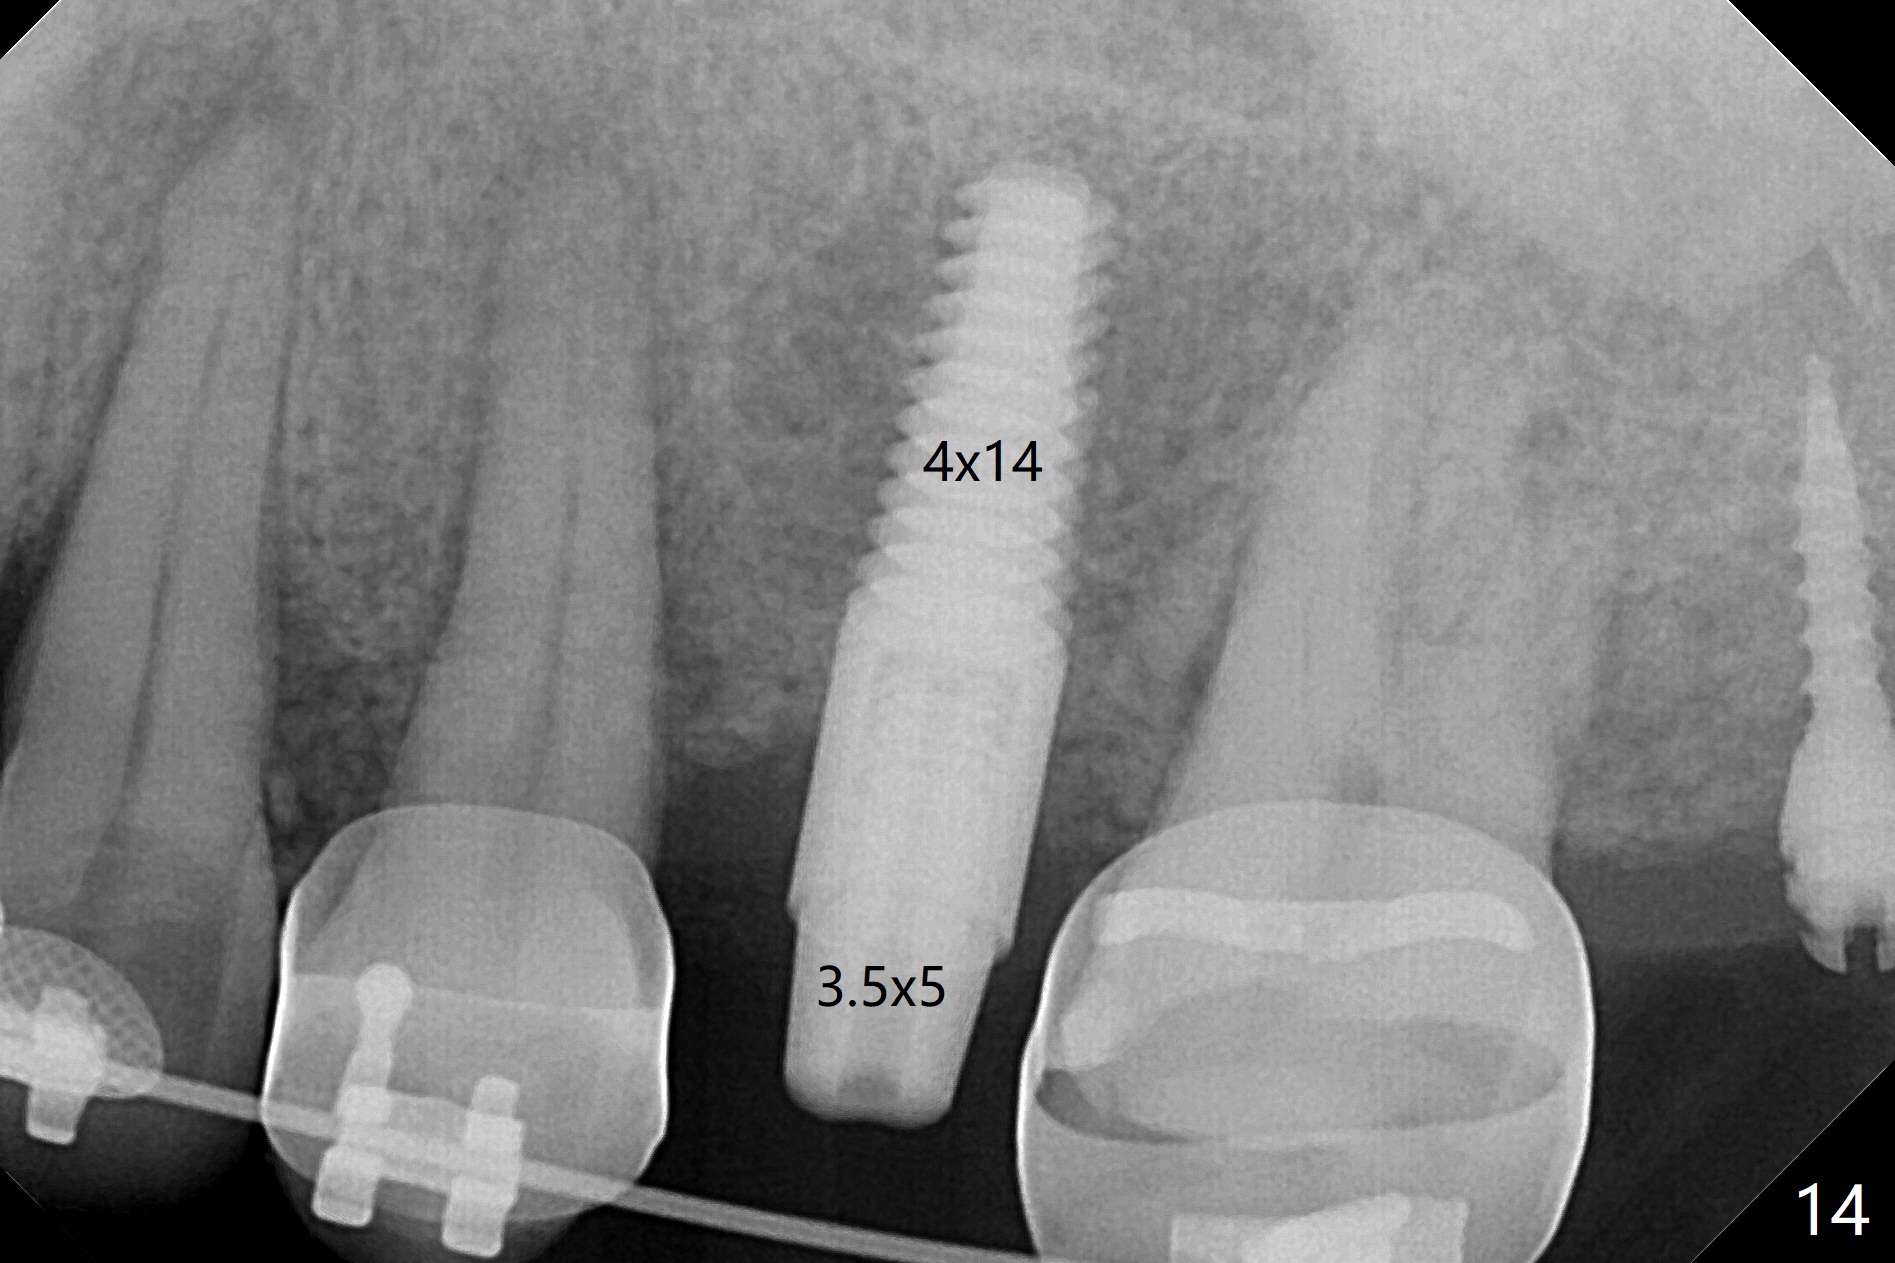

为了在左上6,左下7种植,使用右上3至左上5作为支抗推左上7远中,但是六个月效果不显著(图一),CT显示阻生牙(图一,二:8)没有阻挡。7远中植入1.6x8毫米微型植体,不过接近7根尖(图三),微型植体应该改变角度,而且往远中颊侧移位。最后效果不错(图四),植体马上启用(图五),而且同时取模做左下7导板。在微型植体牵引下,左上7的确往远中移位(图六,与图四对比),但是植体松动,马上植入3x10(2)毫米一段式植体,由于8阻挡,后者没有完全就位,稳定性差,没有启动。几天后也脱落。病人急着完成治疗,因为咀嚼困难。补救方法便是拔除阻生牙9(图七:x),让植体完全就位。切开后发现牙槽嵴处严重骨质吸收缺损(图八:D),离7很近,不适合种植。拔除8后(图九:S(socket)),两处植骨(粘性,图十),覆盖PRF膜,缝合。矫正九个月6空间相当双尖牙(图十二),还想增加2毫米才种植,病人急于完成治疗,所以再次植入微型植体,不同之处是切开,发现7远中颊侧骨质密度低(用探针),因此微型植体在腭侧植入(图十一:P),扭力似乎高,1.6x8毫米植体仿佛植入8牙槽窝(图十二:红虚线)。微型植体牵引一个月,磨牙缺牙间隙大约前磨牙大小,准备在远中(图十三)植入直径小植体(图十四),当后者整合时,用它继续推7。